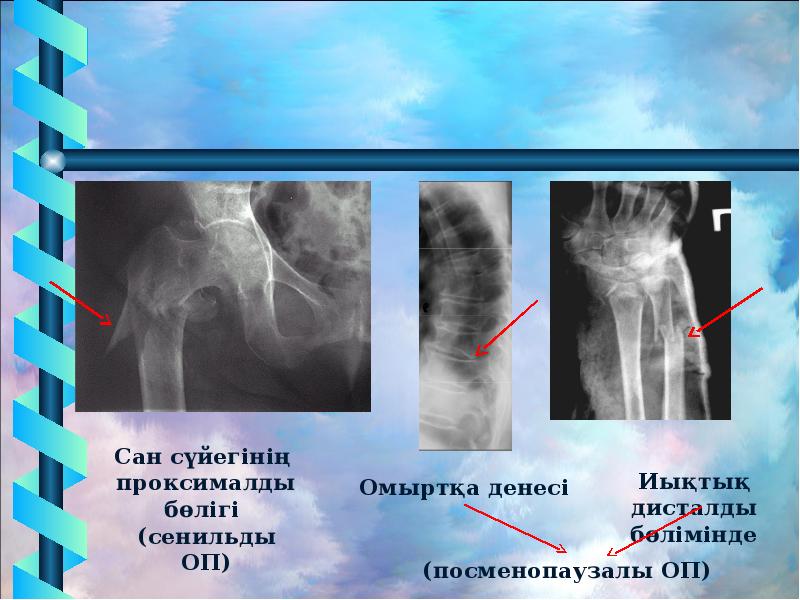

Иллюстрации и схемы по остеопорозу и паращитовидной железе